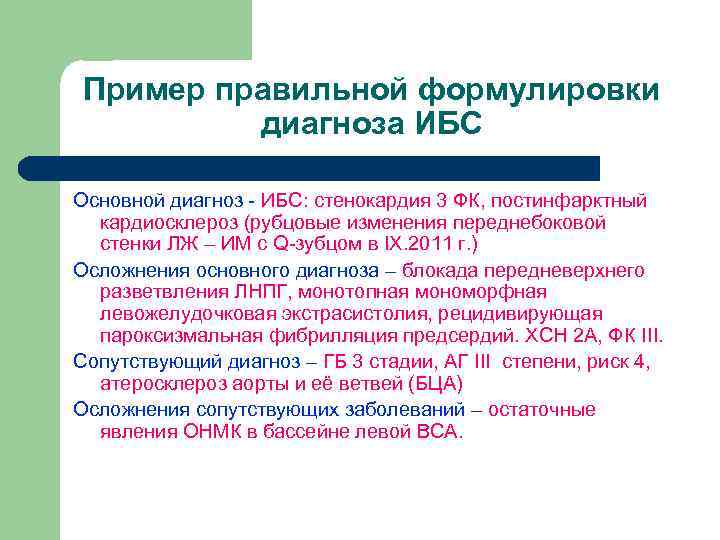

Пример правильной формулировки диагноза ИБС Основной диагноз - ИБС: стенокардия 3 ФК, постинфарктный кардиосклероз (рубцовые изменения переднебоковой стенки ЛЖ – ИМ с Q-зубцом в IX. 2011 г. ) Осложнения основного диагноза – блокада передневерхнего разветвления ЛНПГ, монотопная мономорфная левожелудочковая экстрасистолия, рецидивирующая пароксизмальная фибрилляция предсердий. ХСН 2 А, ФК III. Сопутствующий диагноз – ГБ 3 стадии, АГ III степени, риск 4, атеросклероз аорты и её ветвей (БЦА) Осложнения сопутствующих заболеваний – остаточные явления ОНМК в бассейне левой ВСА.